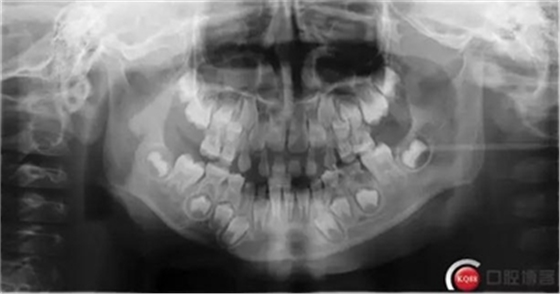

檢查:*75殘冠穿通髓腔,質(zhì)軟,叩診(++),溫度測試無反應(yīng),X線顯示遠(yuǎn)中根已完全吸收、近中根吸收至根頸1/3,且根尖可見低密度暗影。

診斷:*75牙體缺損+根尖周炎